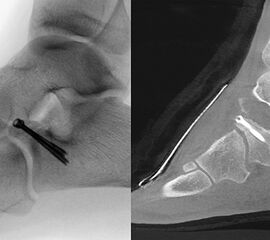

Die Versorgung der Processus anterior calcanei Frakturen erfolgt in der Regel über einen anterolateralen Zugang (alternativ Ollier-Zugang). Unter Schonung der Peronealsehnen sowie des N. cutaneus dorsalis intermedius erfolgt die Darstellung des Lig. bifurcatum. Die Fraktur sowie Gelenkflächen des CC-Gelenks werden sorgfältig inspiziert. Anschließend erfolgt die Reposition des Fragments/der Fragmente. Hierbei kann das Einbringen eines Kirschner-Drahts als „Joystick“ für die anatomische Reposition, insbesondere der CC-Gelenksfläche, hilfreich sein. Die Versorgung erfolgt mittels (Mini-/Kleinfragment-)Zugschrauben-Osteosynthese 11. Wie oben bereits aufgeführt bestehen nicht selten begleitende Bandverletzungen. Daher sollte im Anschluss an die osteosynthetische Versorgung stets eine Prüfung der Bandstabilität unter dem Bildwandler erfolgen. Bei entsprechender Instabilität wird eine temporäre Transfixation mittels Kirschner-Drähten empfohlen 11.

Zum Lesen der Bildbeschreibung und zur Vollansicht bitte das Bild anklicken. Bild: M. Walther